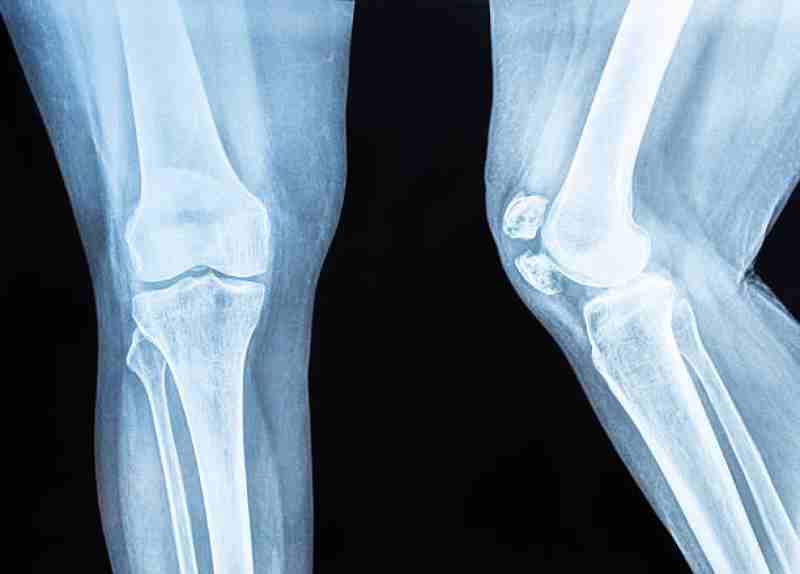

Comprehensive Knee Pain Treatment for Better Mobility

Targeting joint issues requires a deep understanding of anatomy and modern therapeutic options. Whether the cause is an old injury or a chronic condition like arthritis, the goal remains the same: reducing inflammation and restoring fluid movement. Our clinical experts specialize in identifying the specific source of your distress to provide immediate and lasting relief.

Early intervention is the best way to manage joint health and avoid long-term disability. Through professional knee pain treatment, patients can access innovative therapies that promote tissue repair. Our Metro Detroit locations offer a welcoming environment where your recovery is our primary mission, utilizing a blend of traditional and cutting-edge medical techniques.